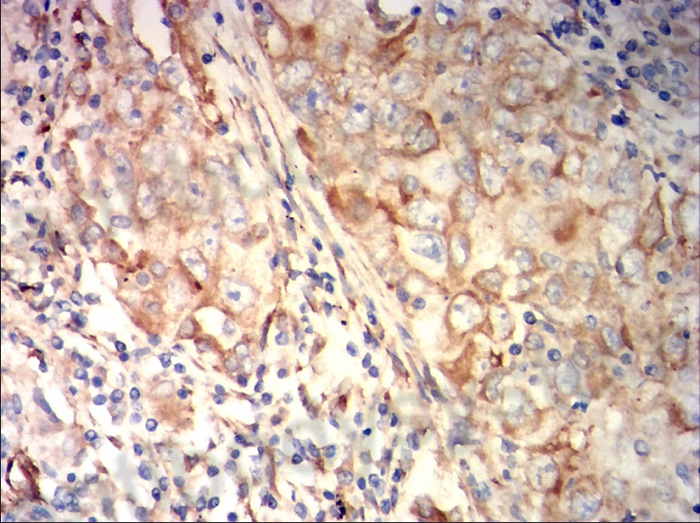

Immunohistochemical analysis of paraffin-embedded lung cancer tissues stained for FGL1/HFREP1 with MHG17901.